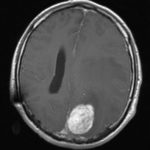

Cette masse peut entrainer notamment :

- Une irritation du cerveau qui se manifeste par une épilepsie

- Une compression voire destruction d’une partie du cerveau causant un affaiblissement ou une perte d’une fonction du cerveau

- Une augmentation de la pression à l’intérieur du crâne (espace inextensible à l’intérieur duquel vient s’ajouter le volume de la tumeur), ce qui va se manifester initialement par des maux de tête d’aggravation progressive qui vont s’associer à des nausées, des vomissements, des troubles visuels… Cet état peut aboutir à la perte de la vue dans les formes d’évolution lente et au décès dans les formes d’évolution rapide.